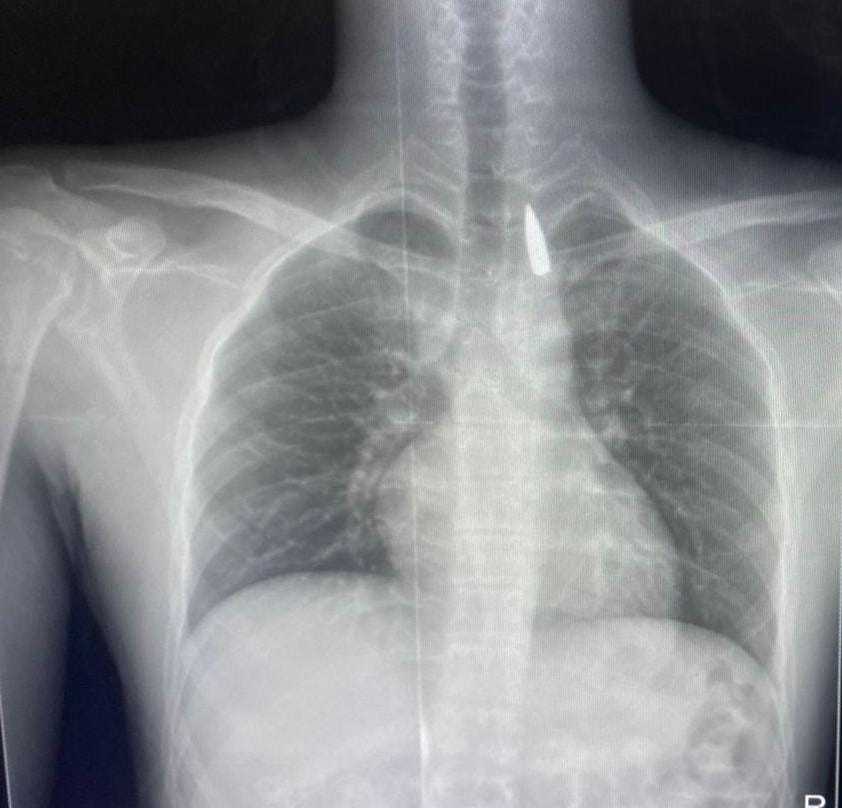

وأوضح تامر عبد الله أن المريض كان قد تعرض لإصابة بطلق ناري في الرأس منذ فترة، استقر المقذوف على إثرها داخل تجويف القفص الصدري قرب الشريان الأورطي، وهو أكبر وأهم شرايين الجسم والمسؤول عن تغذية جميع الأعضاء الحيوية.

وأضاف أن الفريق الطبي، رغم دقة الحالة وتعقيدها، نجح في استخراج المقذوف بأمان بعد عملية جراحية نادرة استمرت عدة ساعات داخل المستشفى الجامعي الجديد، بتاريخ 21 أكتوبر الحالي، حيث خضع المريض بعدها للرعاية الطبية اللازمة، وحالته حاليًا مستقرة وتحت المتابعة الدقيقة من الفريق المختص.